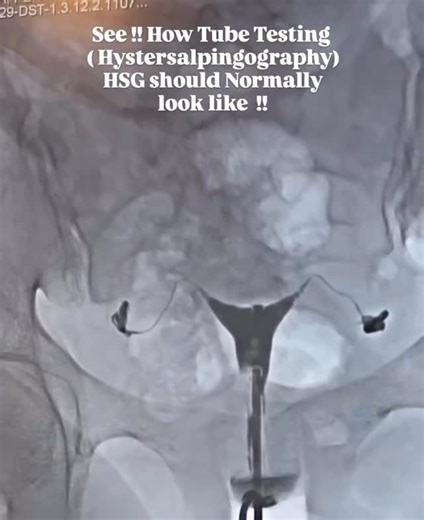

Technique - Normal

HSG Test - HSG

Tube Test - HSG Test